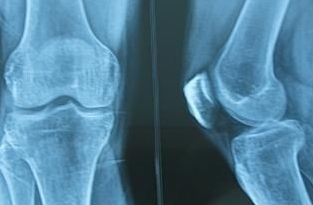

约半数病人出现关节疼痛、肿胀、关节积液。以膝、踝关节受累多见,尚可累及肘、腕、掌指关节和跖趾关节,一般呈不对称性。疼痛以夜间为主,表现为关节轻度酸痛乃至剧烈疼痛。体征包括关节局部发红、发热、触痛、肿胀、关节积液和活动受限,也有表现为无痛性关节积液。在没有大量肌肉覆盖的部位,由于长骨骨膜新骨形成,可致前臂或小腿日益增粗,腕及踝关节亦相应粗大。